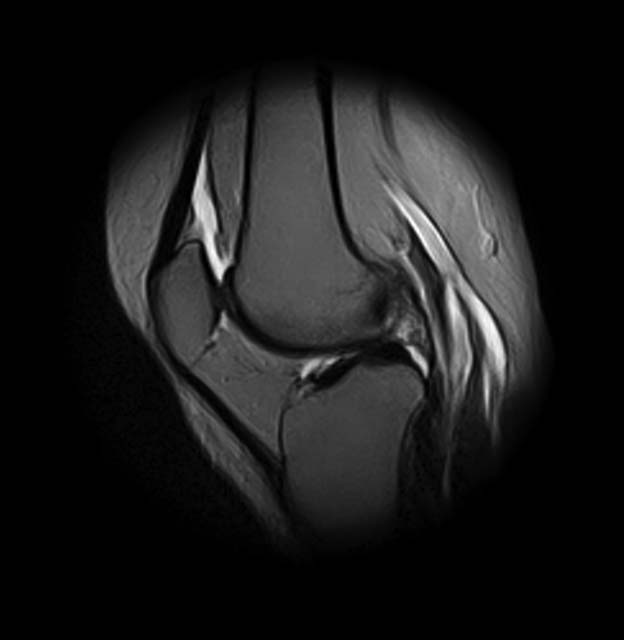

1. травма 5 лет назад - "ударилась коленом", с тех пор боли в суставе

3. стандартные рентгенограммы с небольшими изменениями - сужение

медиальной суставной щели

4. вес пациентки 80 кг, рост 165

5. сустав клинически стабилен